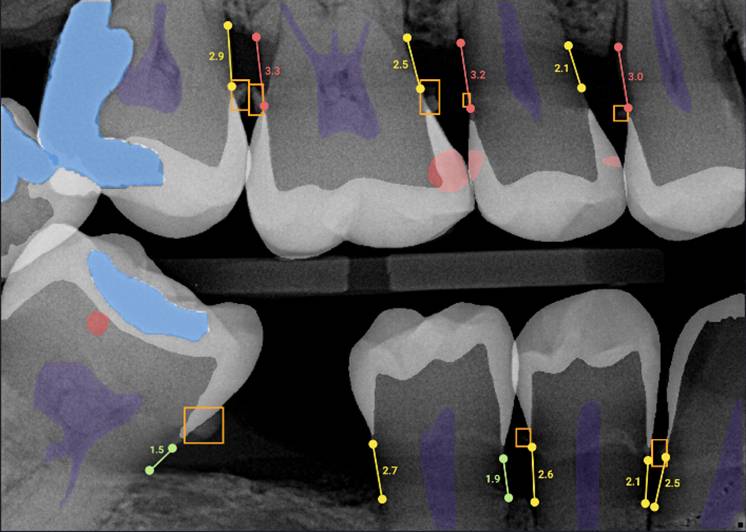

Through years of training, our dentists are experts in reading imaging results, able to see decay, cavities and more on your X-rays. For the lay person, these results are often much more difficult to interpret, even when the dentist is pointing out what he or she is seeing. OVERJET technology analyzes the X-ray images similar to how the dentist would, then overlays that image with colored highlighting and measurements to illuminate any diseases, conditions and more. Essentially, this allows our patients to see what the dentist sees!

Overjet xray

X-Ray with OVERJET